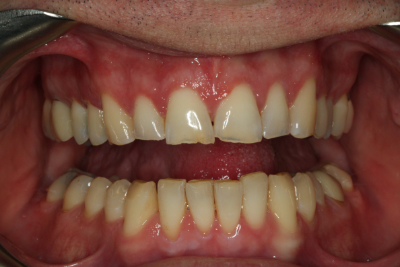

Esthetics, phonetics, and functionを確認した後、最終的な修復を行う準備が整いました。 プロビジョナルレストレーションの写真と印象がラボに渡され、プロビジョナル段階で調整した審美性と咬合を複製し、Darrenの最終修復物に情報を伝達しました。 納品日までに、すでに機能的な問題を診断・治療し、プロビジョナルで治療計画を検証しています。

私たちの目標のひとつは、下顎前歯の準備をせずに、適切な前歯部誘導を達成することでした。 幸いなことに、矯正とダイレクトボンディングの組み合わせで十分すぎるほどの結果が得られたので、今回は下顎弓の修復を見送ることができました。 繰り返しになりますが、私たちの目標は、可能な限り最良の結果を得るために、最小限の歯科治療を行うことです。 時には、包括的な歯科治療を行うために、かなりの量の治療を行うこともありますが、できるだけ多くの歯質を保存するために、保守的であることに挑戦することが重要なのです。

ダレンとの協力により、咬合安定の5つの要件を得るために必要な治療を提供することができました。 現在、彼はすべての歯で安定したストップ、機能の包絡線と調和した前方誘導、前歯が突出した場合の即時後方排除、および作業側と平衡側の突出の干渉をもはや持っていない。